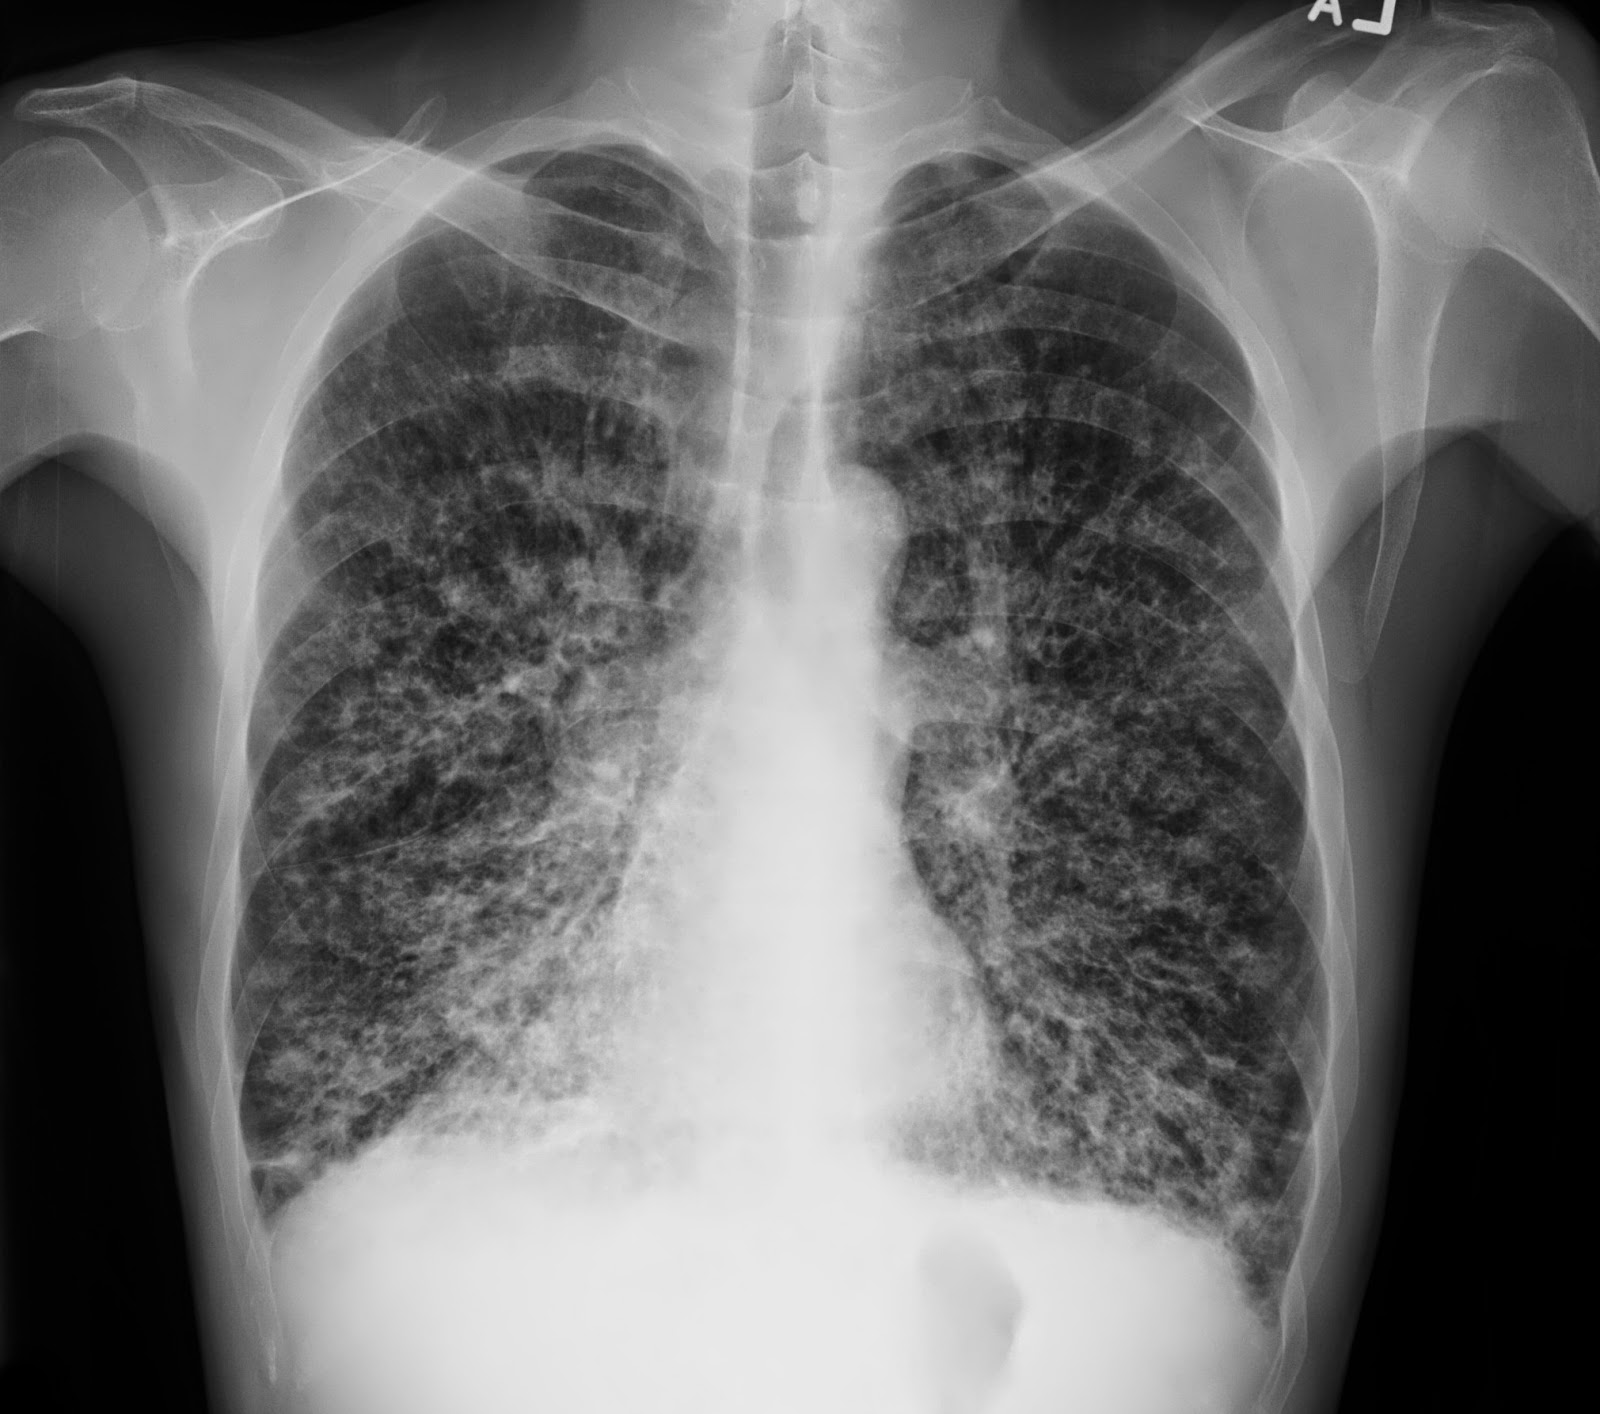

Bronchiectasis Chest X Ray Tram Track . When seen laterally, the bronchiectatic airway has been described. On chest radiographs, bronchiectasis manifests as tram tracks, parallel line opacities, ring opacities, and tubular structures. Chest radiography is usually the initial study performed in suspected bronchiectasis. However, chest radiographs lack sensitivity for detecting mild or. It should not be confused with. 2 findings suggestive of bronchiectasis include “tram track” appearance of dilated bronchi radiating from the hila, bronchial wall thickening. A dilated airway, with thickened airway walls can be noted.